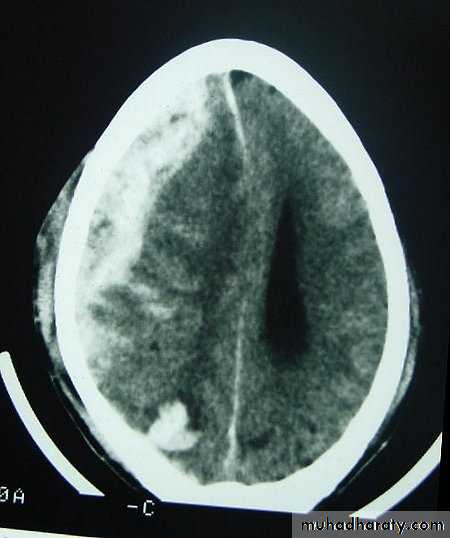

c. Intracerebral Haematoma

This is the least common of traumatic haematoma.

They are due to areas of traumatic contusion coalescing into a contusional haematoma.

Disrupted cerebral tissue release thromboplastins that potentiate haemorrhage.

CT scan: appear as hyperdence lesions with associated mass effect and midline shift.

Large intracerebral haematomas should be evacuated unless the patient’s neurological state is improving.

Small inracerebral haematomas may not require removal, but be aware that they can expand.